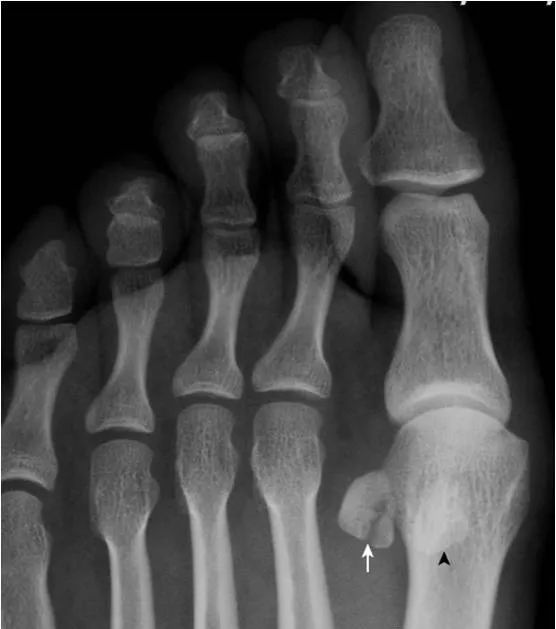

33.籽骨骨折:

拇趾外侧籽骨形态不完整,内侧见透亮线(箭),两部分骨对应缘不规整,无硬化缘,与二分籽骨的边缘骨质致密不同。内侧籽骨完整(箭头)。